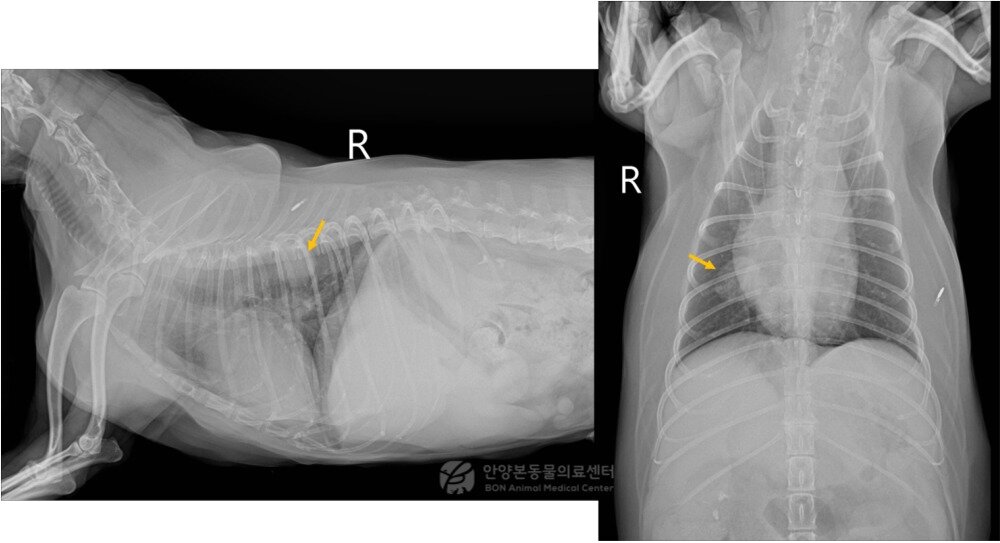

본문 이미지 - 엑스레이 검사 결과 우측 폐 후엽 부위에서 발견된 종괴(본동물의료센터 제공) ⓒ 뉴스1

엑스레이 검사 결과 우측 폐 후엽 부위에서 발견된 종괴(본동물의료센터 제공) ⓒ 뉴스1